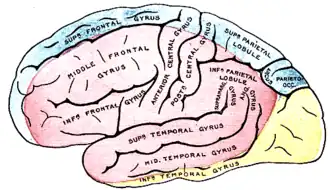

Наружная (внешняя) поверхность больших полушарий головного мозга, показывающая области, кровоснабжаемые теми или иными мозговыми артериями. Жёлтым показана область, кровоснабжаемая задней мозговой артерией. | |